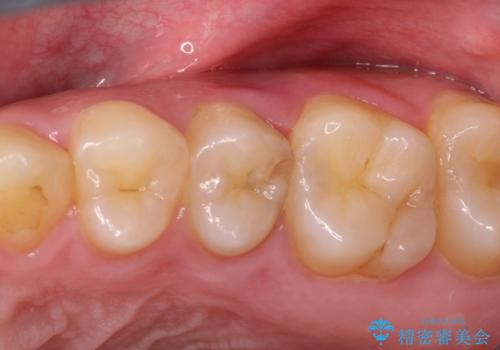

- 奥歯がズキズキ痛いことを主訴に来院されました。

根管治療を行なったのち、オールセラミッククラウンにて修復治療を行なっております。